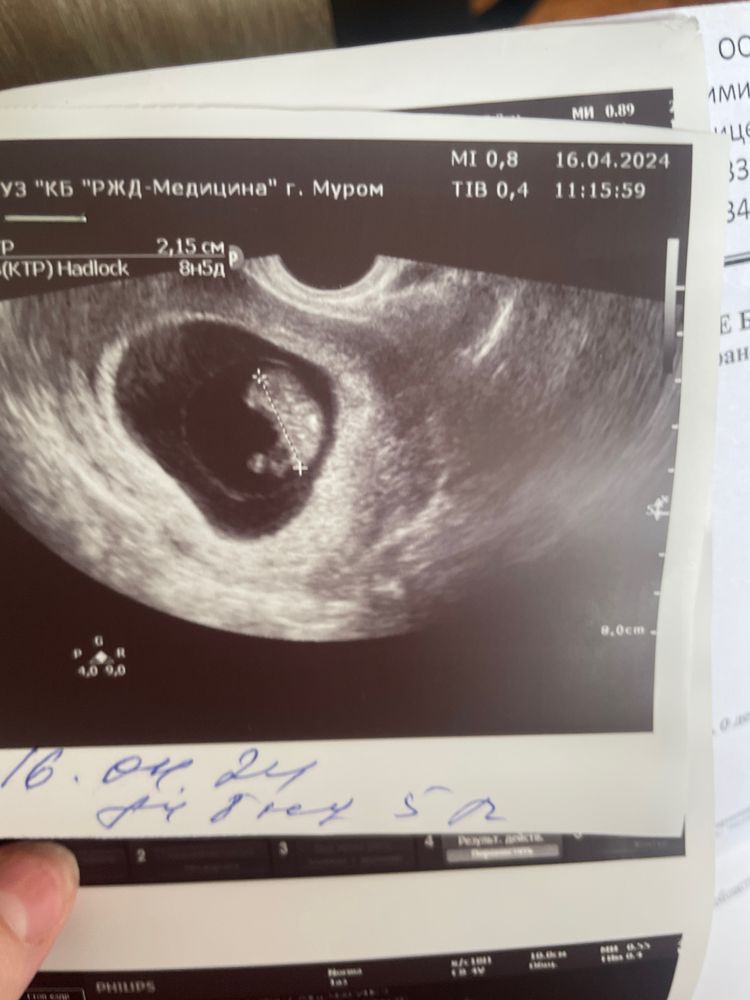

9 неделек😍